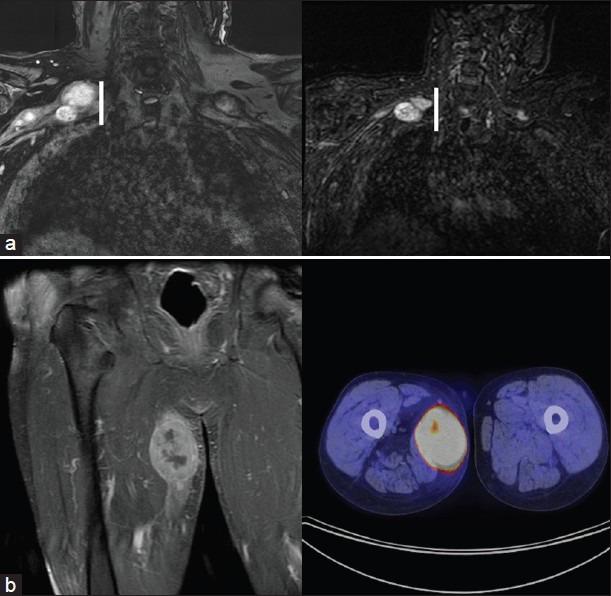

https://cdn.ncbi.nlm.nih.gov/pmc/blobs/a4ca/3868976/c15695764548/SNI-4-407-g001.jpg